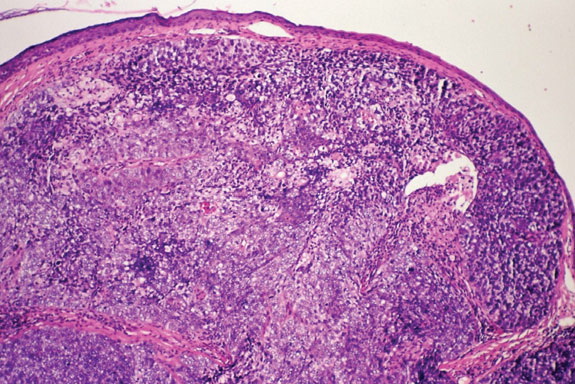

Sebaceous carcinoma = الكارسينوما الدهنية